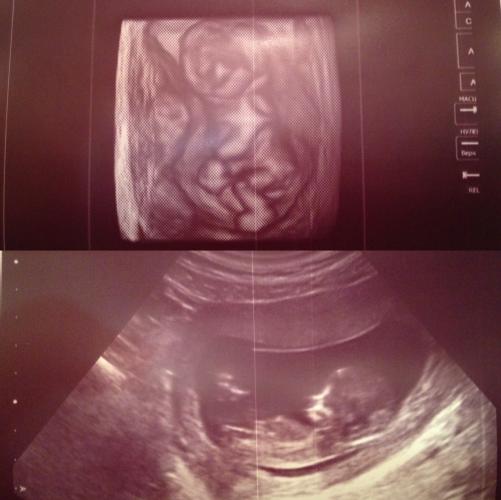

Девчонки, не могу не поделиться, я так рада! Мы вчера ходили на первое УЗИ, а сегодня я сдала кровь. Первый скрининг позади!

Слушайте, это такие непередаваемые ощущения, картинка этого не передаёт. Когда я увидела, как мой ребёночек шевелится у меня в животе во время УЗИ, я насмотреться не могла. Как же это здорово! У него маленькие ручки и ножки, он как куколка... Муж был в шоке, он сказал, что не ожидал увидеть маленького человечка =)

Кстати, нам сказали, что это может быть девочка =)